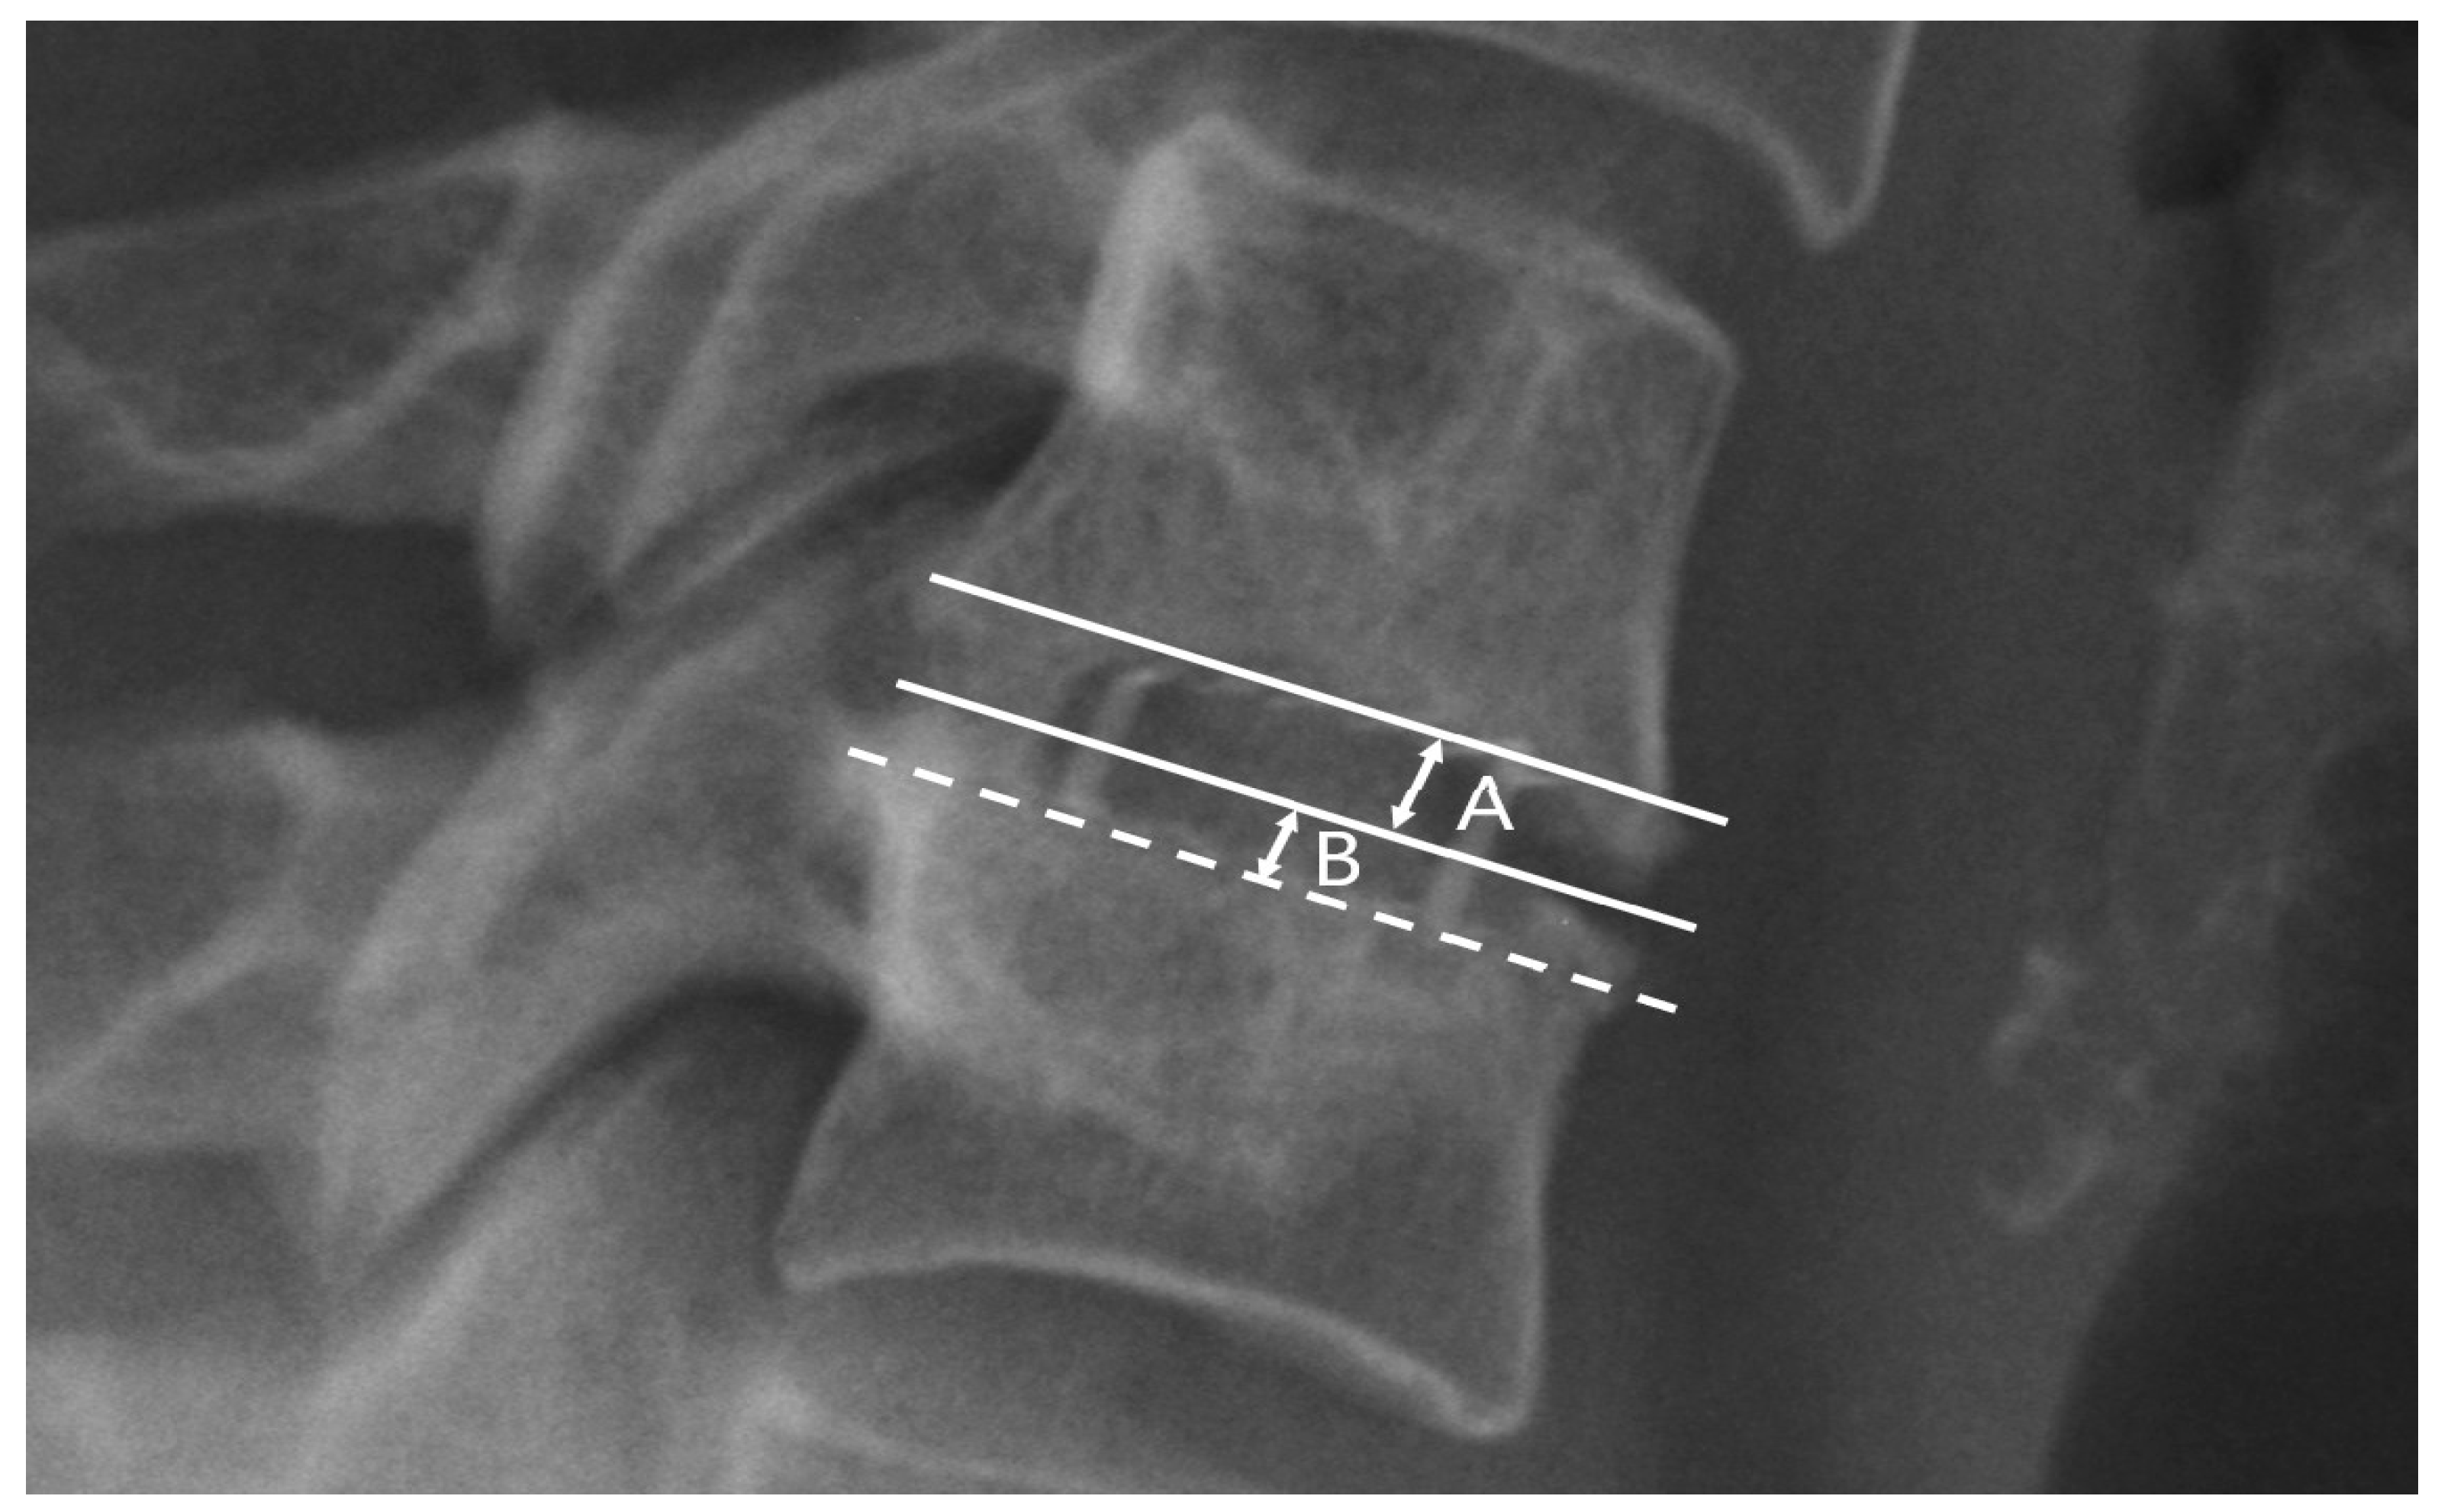

2.3. Radiological Assessment and Subsidence Criteria